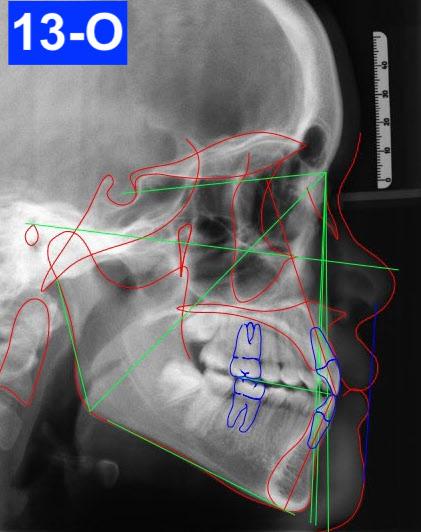

Lateral Cephalometric radiogram and tracing revealed a wide pharyngeal airway (10.0 /10.0 mm), CVMS 3-4, a prognathic maxilla (SNA - 85°), and an orthognathic mandible (SNB - 82 °). Furthermore, a Class I skeletal relationship was noted (ANB – 2.9 mm, Witts – 0.5 mm). The patient was slightly hyperdivergent (NS/GoM – 34°, ALFH – 71.8 mm), exhibited protrusive maxillary incisors (U1/SN – 118.8 ° ) with normally inclined mandibular incisors (L1/GoM 93.5°). The Harvold was 30.5 mm suggesting a Class III tendency. The soft tissue profile (lips) was convex and her Nasio-labial angle (96°) was acute (Figure 5-B).

Although the treatment was disrupted due to the COVID-19 epidemic and despite poor compliance and cooperation, our outcome was favourable. The patient was finished with a skeletal class I, Class III tendency and Angle Class I cuspid and molar relationship with minimal overjet and overbite. ANB improved from 2.9° to 2°. However, the Wits value suggested the patient had grown into a Class III relationship (0.5 mm to -4.4mm). ALFH stayed almost the same, from 72 mm to 72.6 mm.

This patient’s anterior open bite was dental in origin and resulted from an unusually prolonged thumb-sucking habit. When her thumb was not in her mouth, the patient was observed to have aberrant tongue posture during swallowing. Following the treatment, the position of the maxillary anterior teeth was more favourable, U1/SN from 118° to 102°, however, less favourable in the mandible as L1/GoM went from 93° to 86.3°. This effect on the anterior teeth was likely caused from a palato-lingual moment of force from the box elastics. The Naso-labial angle became more acute from 96° to 83°. The Facial axis (Growth axis – Ricketts) stayed almost the same, from 92° to 91°. The soft tissue profile remained slightly convex (lips to S line – Steiner).